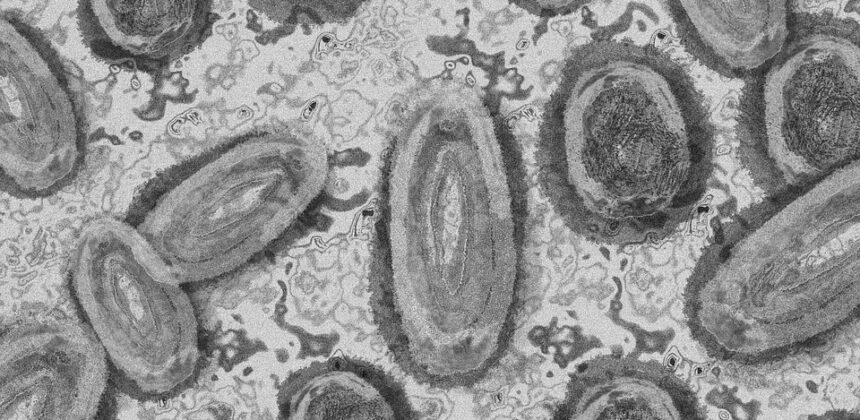

A Monkeypox é uma doença causada pelo vírus Monkeypox do gênero Orthopoxvirus e família Poxviridae. A sua transmissão para humanos pode ocorrer por meio do contato com animal ou humano infectado ou com material corporal humano contendo o vírus. A transmissão entre humanos ocorre principalmente por meio de contato pessoal com secreções respiratórias, lesões de pele de pessoas infectadas ou objetos recentemente contaminados.